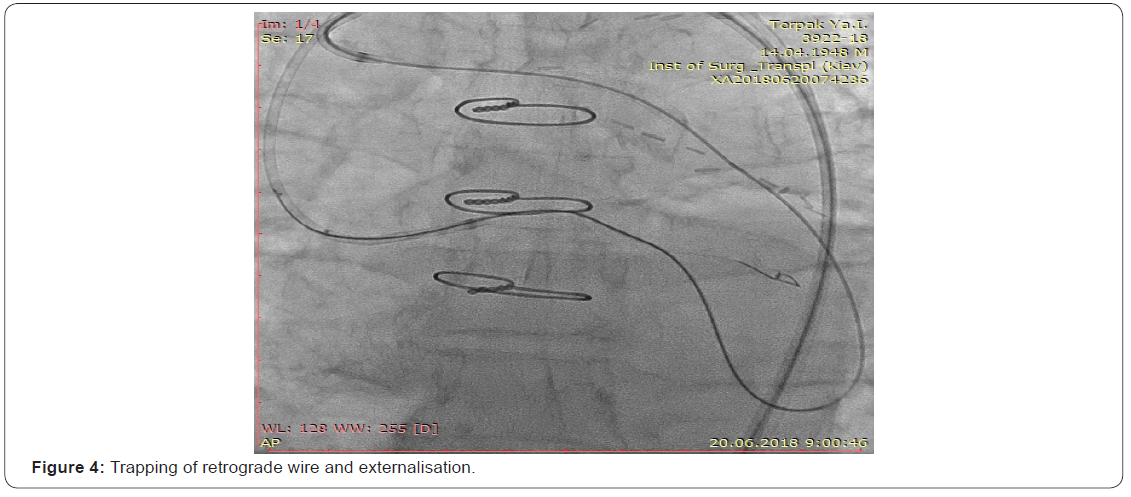

The next step after the removal of the retrograde instruments it was used “Guidezilla” 6F guide catheter extension, dilatation with the 1.5 “Trek” balloon catheter (Figure 3), and after that retrograde microcatheter could cross CTO site and was fixed into an antegrade guide and an externalization procedure was performed using the RG 3 guidewire (Figure 4). Further, after balloon angioplasty with a balloon catheter of 2.5 mm, an attempt was made to implant the stent in the CX, but in view of the calcified site, the stents could be implanted only with the use of the “Guidezilla” 6F catheter extension in antegrade fashion.